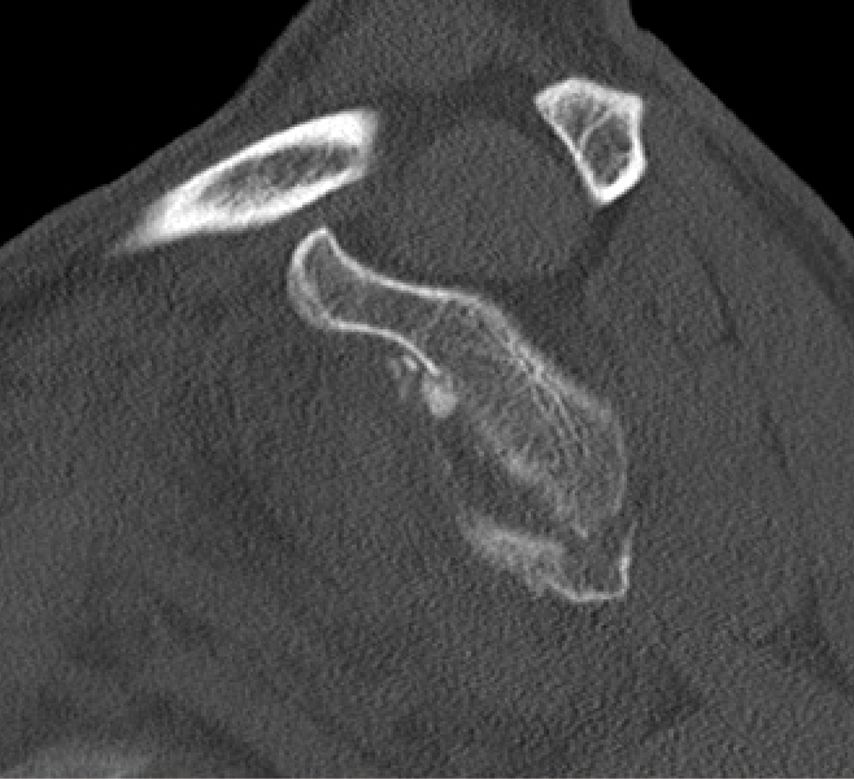

Die operative Versorgung ist indiziert bei instabilen Frakturen mit Subluxation des Humeruskopfes, großem knöchernem Defekt oder erheblichem Stufenversatz. Als Grenzwerte werden in der Literatur häufig eine Fragmentgröße von mehr als 20% der Glenoidfläche sowie ein Stufenversatz von über 5mm genannt (Itoi; Abb. 1 und 2).

Die arthroskopische Refixation hat sich als minimalinvasives Verfahren zur Versorgung selektierter Glenoidfrakturen etabliert. Insbesondere bei Ideberg-Typ-I-Frakturen (Ia ventral, Ib dorsal), knöchernen Bankart-Läsionen sowie kleinen bis mittelgroßen intraartikulären Fragmenten ermöglicht dieses Verfahren eine anatomische Rekonstruktion bei geringer Weichteilmorbidität. Voraussetzung ist das Vorliegen einer akuten Fraktur innerhalb eines Zeitraums von etwa zwei bis drei Wochen nach Trauma. Darüber hinaus müssen die Frakturfragmente reponierbar und von ausreichender Größe für eine stabile Fixation sein, während ausgedehnte Trümmerfrakturen oder eine relevante Schädigung des Skapulahalses ausgeschlossen sein sollten. Relative Kontraindikationen sind ausgeprägte Impressionen, chronische Frakturen mit Fragmentresorption sowie multidirektionale Schulterinstabilitäten. Eine sorgfältige präoperative Planung ist essenziell und basiert auf einer Computertomografie mit dreidimensionaler Rekonstruktion. Diese ermöglicht eine präzise Analyse der Fragmentgröße, der Dislokationsrichtung sowie des prozentualen Defektanteils der Glenoidfläche. Auf dieser Grundlage erfolgt die Festlegung der operativen Strategie, insbesondere die Wahl zwischen Schraubenosteosynthese und Fadenankerrefixation sowie die Planung der Anzahl und Position der arthroskopischen Portale.